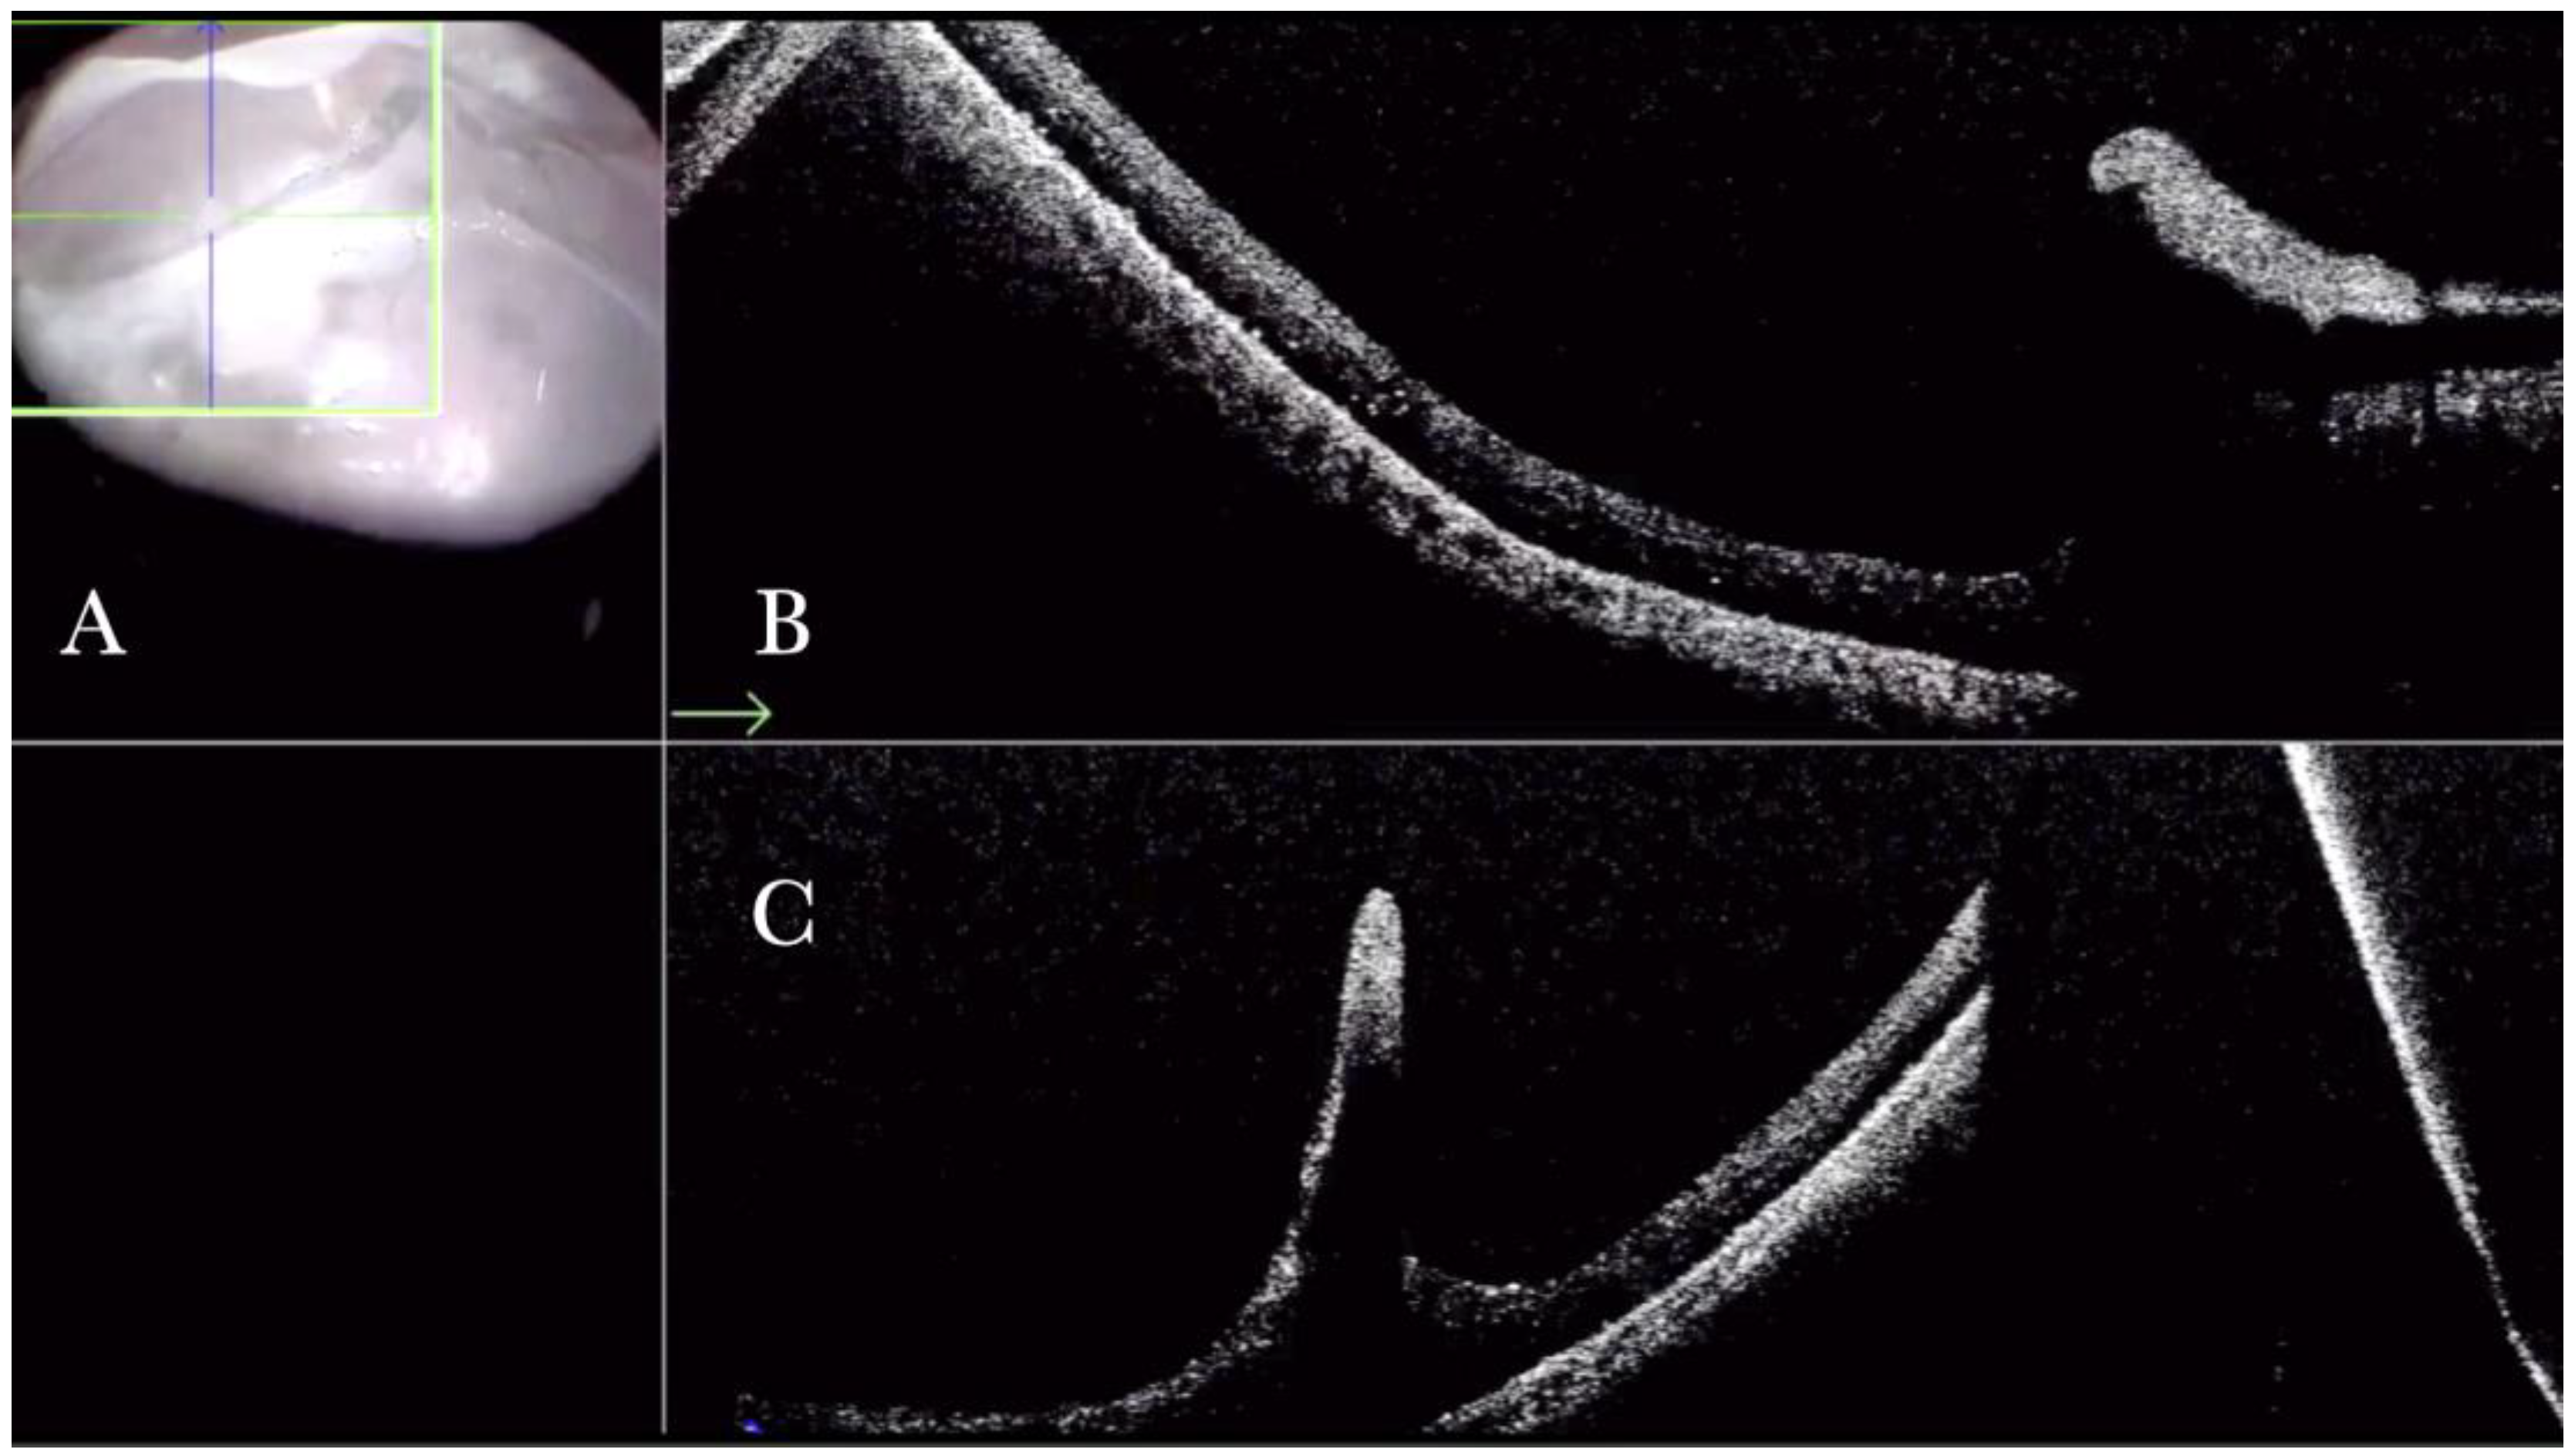

MTM in any stage, according to the MTM staging system (MSS), is one of the most challenging diseases. Among the different surgical options for MTM, the macular buckle represents a satisfactory option that can be used alone to treat cases of maculoschisis (MSS stage 2) or macular detachment (MSS stage 3 or stage 4), or in combination with vitrectomy when holes are present (MSS stage c) [20]. The macular buckling technique requires precise centration of the buckle in the area of interest. However, we can usually assess its position through the microscope through the panoramic viewing system. The i-OCT confirms the position of the buckle under the fovea and the height of indentation (Supplementary Material Video S9 and Figure 10) and enhances areas with holes centered on the buckle both when working under fluid (Figure 11) and under air (Figure 12).

Figure 10.

(A) Microscope view of the macular area in case of myopic traction maculopathy in stage 3a (macular detachment and no macular hole) after implanting a macular buckle. The transillumination of a fiber optic inserted into the buckle allows us to identify the location of the buckle itself. (The green box indicates the field-of-view of the OCT scan, the green and blue lines within the green box show the vertical and horizontal scan planes). (B) The intraoperative optical coherence tomography (i-OCT) B horizontal (green arrow) scan shows, very clearly, the indentation of the macula from the scleral side due to the presence of a macular buckle. (C) The i-OCT B vertical (blue arrow) scan shows, very clearly, the indentation of the macula from the scleral side due to the presence of a macular buckle.

Figure 11.

(A) Microscope view of the macular area in case of myopic traction maculopathy in stage 4C (macular detachment with full-thickness macular hole (FTMH)) after implanting a macular buckle. The transillumination of a fiber optic inserted into the buckle allows us to guess the location of the buckle itself. The inner limiting membrane (ILM) flap is visibly stained blue. The FTMH is not visible. (The white box indicates the field-of-view of the OCT scan, the green line within the green box shows the scan plane) (B) The Intraoperative Optical coherence tomography (i-OCT) B horizontal (green arrow) and vertical scan shows very clearly the indentation of the macula from the scleral side due to the presence of a macular buckle. The white arrowhead shows the FTMH, which is not over the buckle. (C) Same view as in A after repositioning the macular buckle. (The white box indicates the field-of-view of the OCT scan, the green line within the green box shows the scan plane) (D) i-OCT B horizontal (green arrow) and vertical scan showing very clearly the indentation of the macula from the scleral side due to the presence of a macular buckle. The white arrow shows the FTMH, which is now well-positioned over the buckle.

Figure 12.

(A) Microscope view of the macular area in case of myopic traction maculopathy in stage 4C (macular detachment with full-thickness macular hole (FTMH)) after implanting a macular buckle and peeling the inner limiting membrane (ILM) creating an ILM flap. The transillumination of a fiber optic inserted into the buckle allows us to guess the location of the buckle itself. The FTMH is not visible under the air. (The green box indicates the field-of-view of the OCT scan, the green and blue lines within the green box show the vertical and horizontal scan planes). (B) The intraoperative optical coherence tomography (i-OCT) B horizontal (green arrow) scan shows, very clearly, the indentation of the macula from the scleral side due to the presence of a macular buckle. (C) The i-OCT B vertical scan shows, very clearly, the indentation of the macula. The white arrow shows the FTMH, which is now well-positioned over the buckle, and the presence of the ILM flap even under the air.